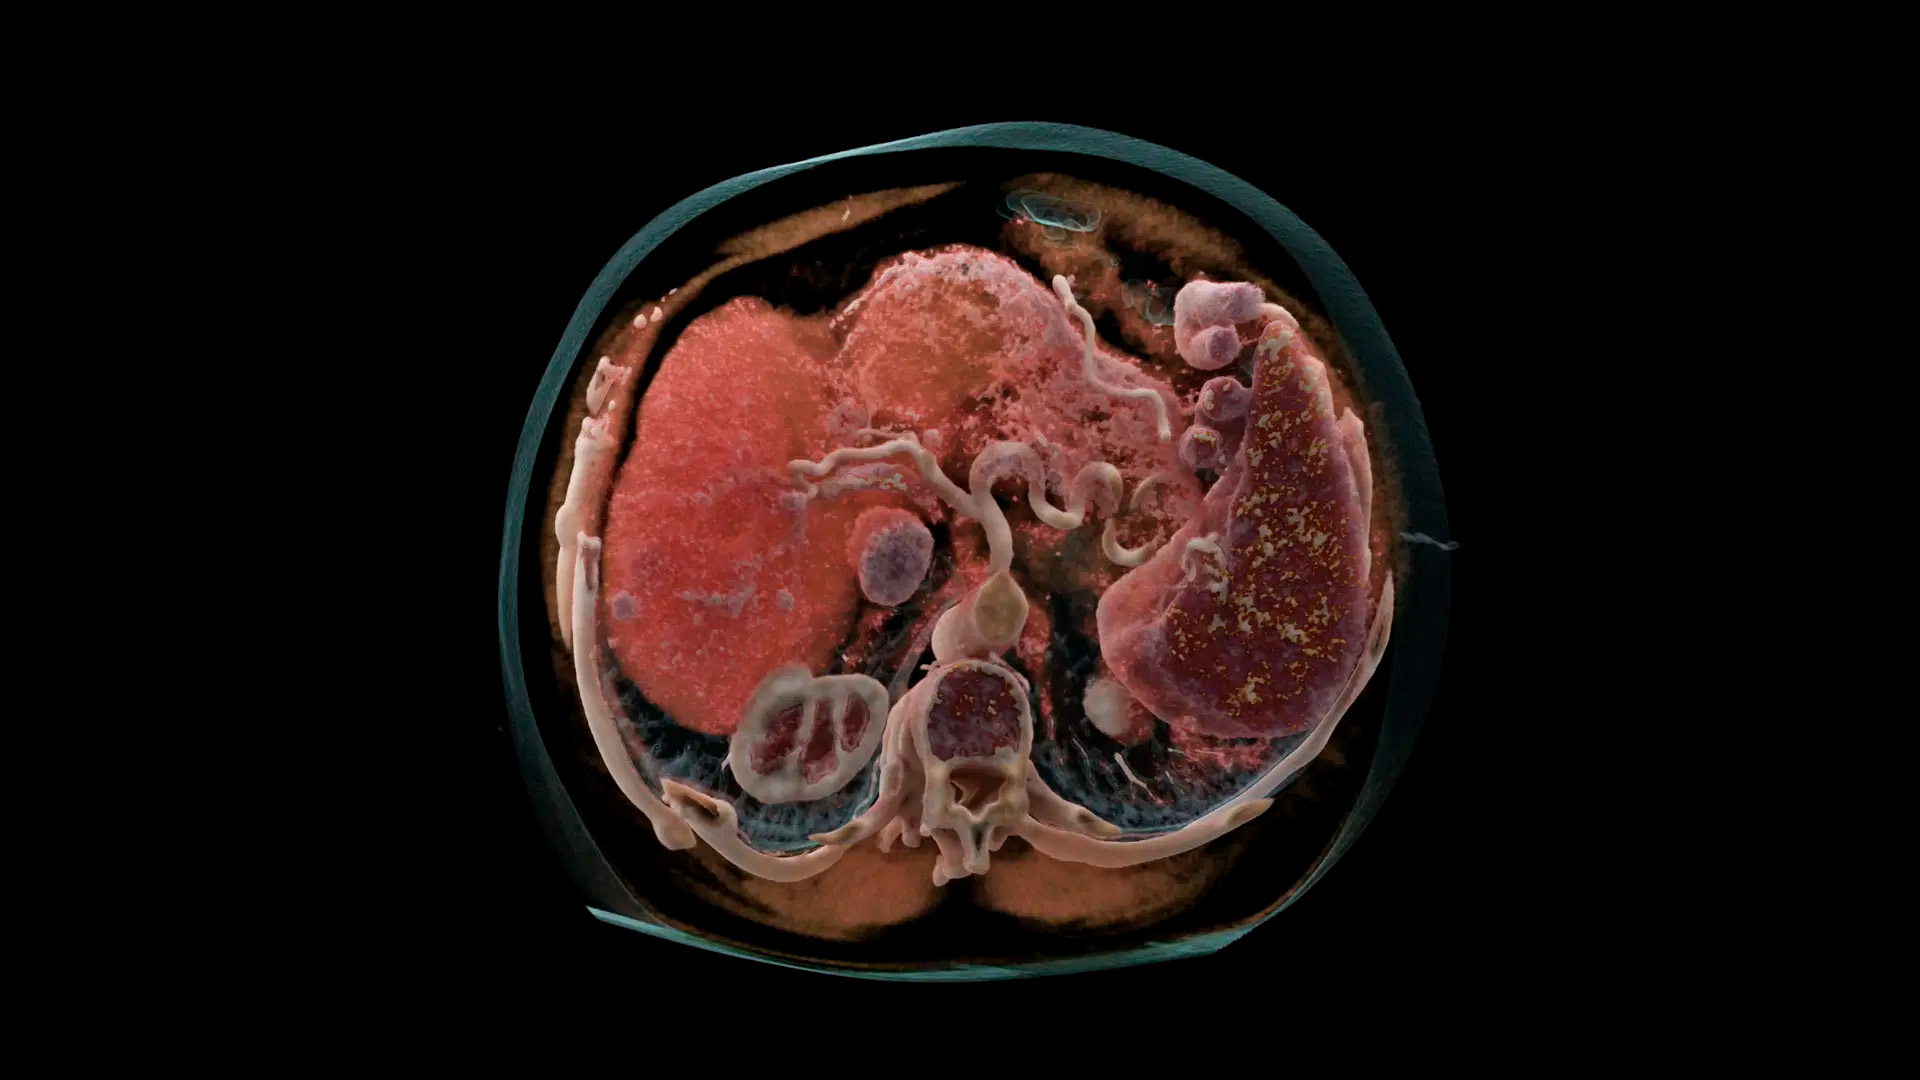

Клинические изображения

NAEOTOM Alpha с квантовой технологией знаменует начало новой эры в КТ. Невиданная ранее технология призвана помочь в принятии клинических решений для большего числа пациентов.

В основе NAEOTOM Alpha ® лежит радикально новый детектор. Детектор QuantaMax напрямую преобразует рентгеновские лучи в электрический сигнал, который затем используется для создания изображения. Измеряется энергия каждого рентгеновского луча, поэтому спектральная информация доступна для каждого сканирования, а изображения получаются контрастными и с высоким пространственным разрешением при той же дозе. Сочетание высокого пространственного разрешения детектора подсчета фотонов QuantaMax с временным разрешением двойного источника позволяет визуализировать мелкие детали для повышения достоверности диагностики.

Внедрение квантовой технологии в рутинный КТ-сканер позволяет совершить клинические прорывы, недостижимые с помощью традиционной КТ-технологии, и обеспечивает высокую диагностическую достоверность, необходимую для принятия решений.

Получайте спектральные карты при каждом сканировании, независимо от скорости сканирования, поля обзора или пространственного разрешения. Это обеспечивает точную функциональную оценку без каких-либо компромиссов.